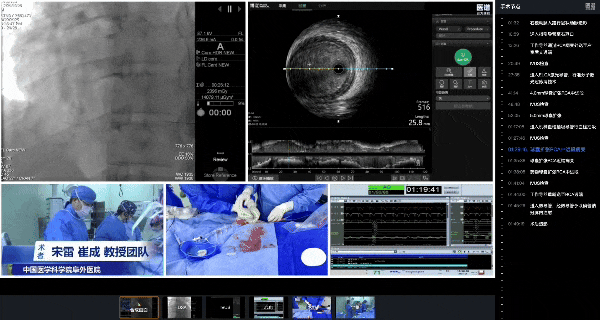

全景手术复盘|宋雷教授、崔成教授深度解析激光消蚀与血栓抽吸术在复杂冠脉病变中的应用

随着精准诊疗理念深化,复杂冠脉病变介入治疗已不再局限于手术的即刻成功,而是更加注重远期预后。这对介入医生的策略制定、技术运用和术中应变能力提出了更高的要求。在此背景下,由阜外医院冠心病一病区牵头、联合介入导管室、医谱学术全新打造的全景手术复盘系列课程应运而生,该课程以多视角影像采集与时序化节点同步为核心,实现了复杂手术全流程的可视化、可标记的真实临床教学模板。

通过“主刀视角+操作影像同步+关键节点深度解构”三位一体的全景教学模式,将复杂手术的操作细节、策略选择与术中应变精准还原,为医生提供了手术全程高效学习和复盘的系统工具,推动先进技术与规范理念向基层持续普惠。

9月18日,全景手术复盘系列课程首期教学内容在阜外医院宋雷教授主持下,崔成教授通过一例“高血栓负荷编织样血管介入治疗”的特殊病例复盘,深入解析了激光开通血管的策略选择与操作要点,并展示了血栓抽吸术在快速恢复冠脉血流、减少远端栓塞中的关键技巧,为临床复杂冠脉病变应对处理探索了新策略。

过导丝并评估血管内部情况

随后,IVUS评估显示,右冠脉管径过大,且机化血栓负荷重,如直接植入支架/放置药球可能导致支架贴壁不良/药球膨胀不全及血流恢复不佳等,决定在支架植入/药球放置前先行血栓消蚀。

4mm球囊扩张后IVUS检查